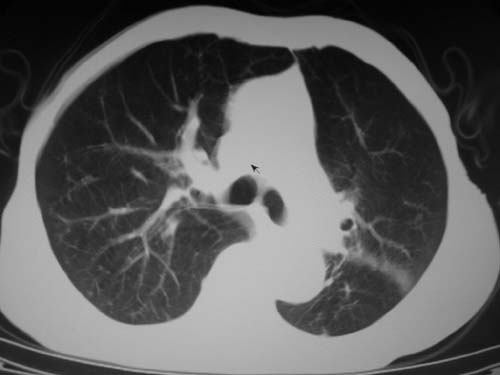

标题: CT19736:男,76岁,咳嗽,胸痛 [打印本页]

标题: CT19736:男,76岁,咳嗽,胸痛

周围型肺癌?坏死性肉芽肿?

支持左上肺周围型肺癌性并空洞形成伴胸椎转移。

左上沟癌空洞形成并胸椎转移。

考虑癌性空洞并胸椎转移。

空洞内壁有多发结节,支持癌性空洞。